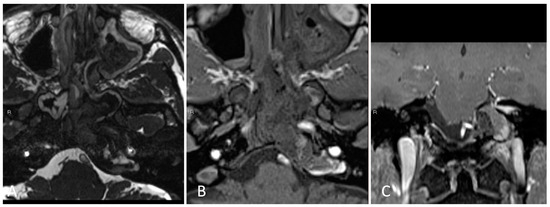

3.2. Orbital Apex

3.2.2. Illustrative Case

3.2.3. Practical Pearls

- The goals of surgical resection for metastatic lesions to the orbit are to obtain decompression of the optic apparatus and to obtain a diagnosis.

- The periorbita should be opened parallel to the medial rectus muscle to minimize inadvertent injury.

- In the medial endonasal approach, the two corridors include between the superior oblique and medial rectus muscles, as well as between the medial rectus and the inferior rectus muscles.